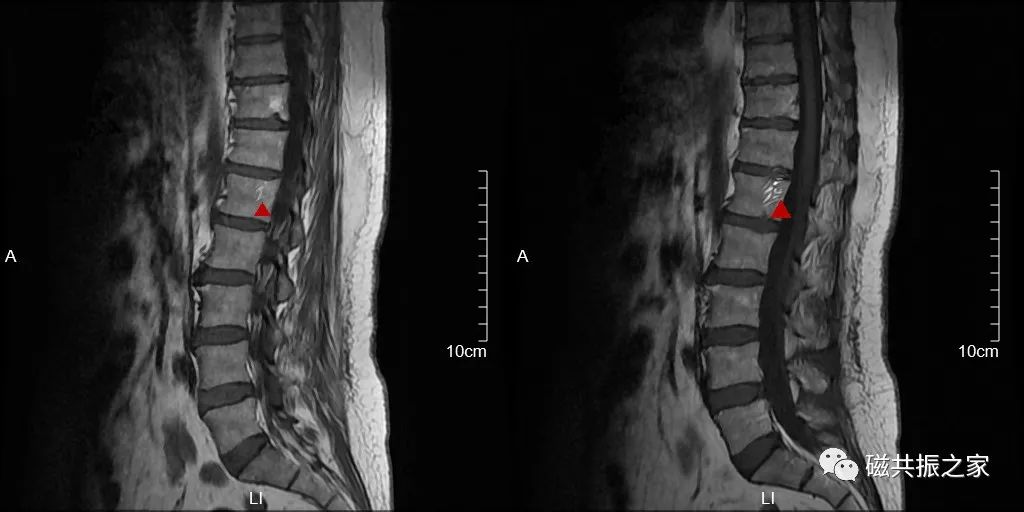

蓝色箭头所指的是由脊髓腔内脑脊液流动所形成的流动伪影,白色箭头所指的则是截断伪影。蓝色和白色箭头所呈现的征象均属于伪影,椎管和脊髓实际上是正常的,而星号区域为 L1 椎体血管瘤。